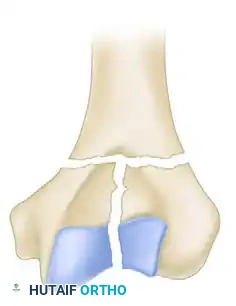

While the AO/OTA classification system is exhaustive (defining 61 types across A, B, and C categories), the Jupiter and Mehne classification, as well as the Mehne and Matta bicolumnar descriptions, offer superior utility for preoperative templating. Mehne and Matta categorize complex bicolumnar fractures based on their geometric configuration:

Mehne and Matta High T-Fracture configuration.